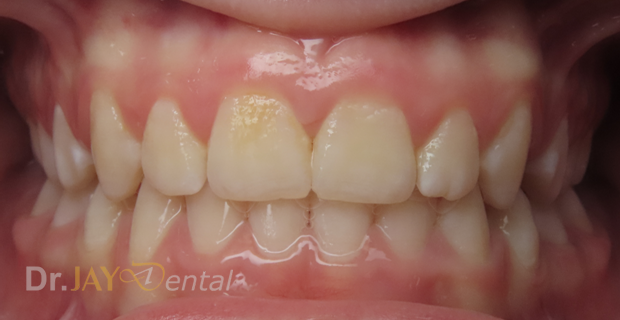

CASE 12

Patient has deep bite , crowding of teeth , narrow jaws , had airway issues. Deepbite corrected, upper and lower jaws expanded , increase in vertical height of the jaws . At our office, myofunctional therapy , using functional appliances created a harmonious balance for patient’s airway and oral structures

Before

After